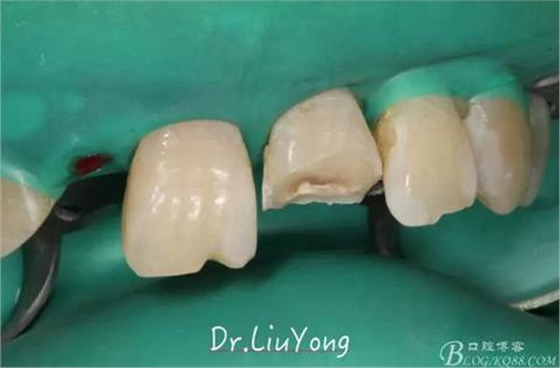

由于上前牙外傷后未及時行松牙固定,已拖延1月,因此先行松牙固定,嘗試保留。因A2冠根折,牙冠缺失,故行A1-B3松牙固定,選擇鄰面樹脂粘結(jié)固定,因為牙齦極易出血,因此選擇橡皮障下用流體樹脂進(jìn)行松牙固定。同時A2B1根管治療。

手術(shù)后1月,決定先行臨時修復(fù),由于患者為重度深覆合,因此考慮將上前牙通過臨時修復(fù)體,降低切端的高度,減輕覆合,同時將舌傾的牙冠形態(tài)調(diào)整為較為直立。B2為根折到齦下1.5mm,考慮到患者無法接受正畸,同時如果近中鄰面行冠延長手術(shù)會帶來后續(xù)的黑三角美觀問題,因此選擇在橡皮障下行齦壁提升,然后A2纖維樁+樹脂核,A1-B2臨時樹脂貼面修復(fù),A2臨時冠修復(fù)。